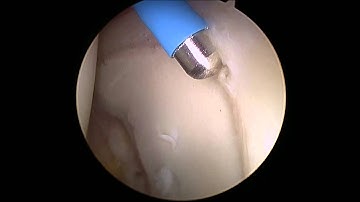

Return to Play with Hip Arthroscopy